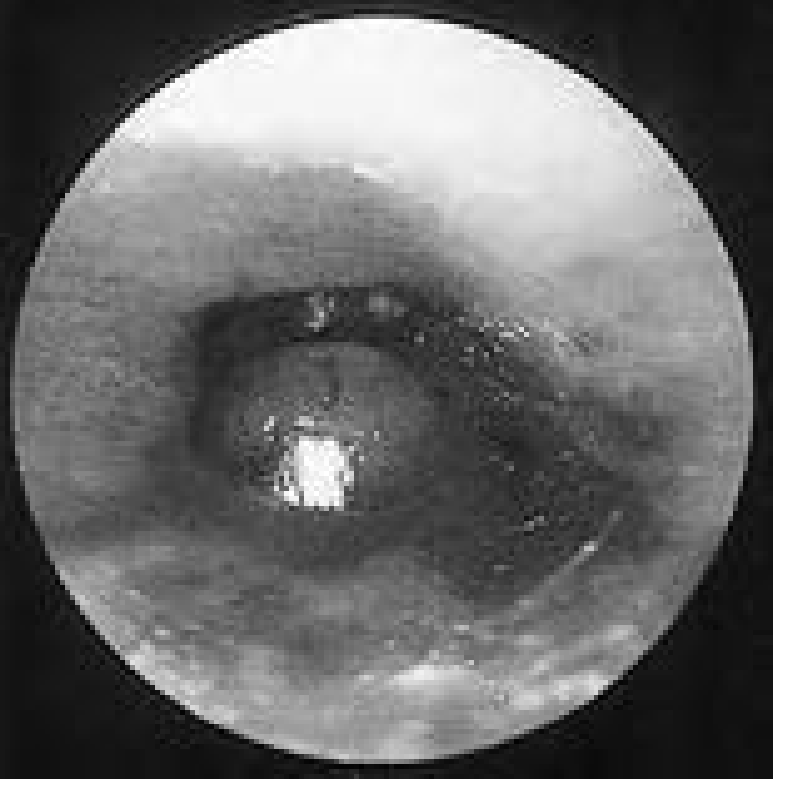

Chronic external otitis with canal atrophy and stenosis

Chronic external otitis: atrophy and stenosis of the canal skin — Cummings Otolaryngology, Fig. 138.1